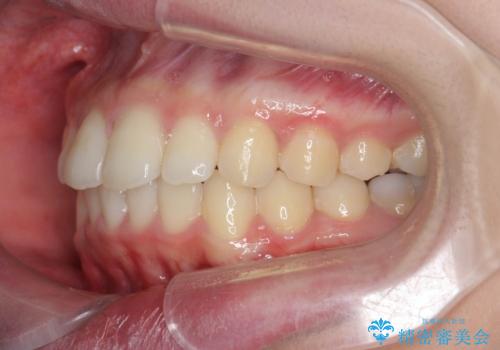

出っ歯を治すマウスピース矯正

- 出っ歯のように見える前歯の角度を治したい、と矯正治療を希望され来院されました。

抜歯をせずにマウスピース矯正システムインビザラインを用いてしっかりと前歯の角度を改善していきます。

前歯の角度だけでなく内側に倒れ込んでいた奥歯もしっかり起こすことで咬合関係も理想的に仕上げています。